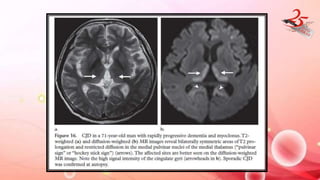

Creutzfeldt –jakob Disease

• Transmissible fatal neurodegenerative disorder caused by prions

• CLINICAL FEATURES : rapidly progressive dementia, myoclonus, and

multifocal neurologic dysfunction.

• DIAGNOSIS: Brain Biopsy /autopsy, periodic charp wave complexes

at EEG

IMAGING FINDINGS:

• MRI : DWI R of cerebral cortex and basal ganglia

• Variant CJD : Bovine spongiform encephalopathy

• B/L lesions in pulvinar nuclei of thalamus(pulvinar sign/hockey stick sign)

Creutzfeldt –jakob Disease •Transmissible fatal neurodegenerative disorder caused by prions • CLINICAL FEATURES : rapidly progressive dementia, myoclonus, and multifocal neurologic dysfunction. • DIAGNOSIS: Brain Biopsy /autopsy, periodic charp wave complexes at EEG IMAGING FINDINGS: • MRI : DWI R of cerebral cortex and basal ganglia • Variant CJD : Bovine spongiform encephalopathy • B/L lesions in pulvinar nuclei of thalamus(pulvinar sign/hockey stick sign)